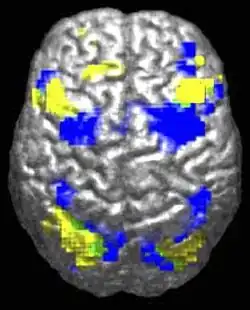

Функциона́льная магни́тно-резона́нсная томогра́фия, функциона́льная МРТ или фМРТ (англ. Functional magnetic resonance imaging) — разновидность магнитно-резонансной томографии, которая проводится с целью измерения гемодинамических реакций (изменений в токе крови), вызванных нейронной активностью головного или спинного мозга. Этот метод основывается на том, что мозговой кровоток и активность нейронов связаны между собой. Когда область мозга активна, приток крови к этой области также увеличивается[1].

ФМРТ позволяет определить активацию определенной области головного мозга во время нормального его функционирования под влиянием различных физических факторов (например, движение тела) и при различных патологических состояниях.